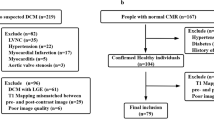

The current study included 82 patients (72% male, 28% female), their ages ranged from 11 to 74 years with mean age 43.46 ± 15.03. Control group (10 healthy volunteers) represent 14% of the cases (70% male, 30% female), their ages ranged from 20 to 50 years with mean age 32.2 ± 9.14 as shown in Fig. 1. The distribution of the studied patients by diagnosis was 69.4% DCM (ischemic 66%, post myocarditis 10%, Duchene 2%, and idiopathic 22% of DCM cases). Sixteen percent were HCM (phenotype distribution 50% septal, 8.3% sigmoid, 16.6 concentric, 8.3% focal mid), 4.1% were amyloidosis, 6.9% were non-compaction, and 2.7% were sarcoidosis of total 72 cases (Figs. 2, 3, 4 and 5).